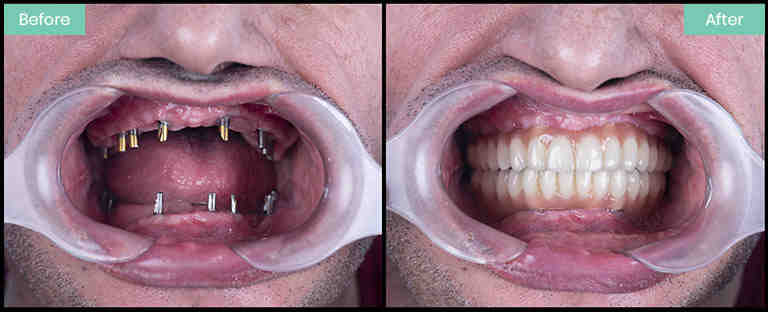

How successful are dental implants

What is the failure rate of dental implants?

What percentage of dental implants are successful?